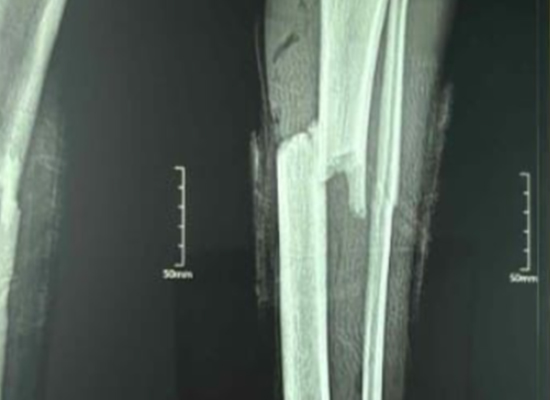

Preoperative imaging revealed a midshaft tibial fracture with mild displacement. A hybrid fixation technique (nail + plate) was selected to enhance mechanical strength and promote safe recovery.

Preoperative X-ray of tibial fracture

During surgery, the intramedullary nail provided axial fixation while the one-third circular plate enhanced lateral stability.

Postoperative Imaging

Postoperative radiographs showed excellent alignment and fixation integrity. The patient began gentle rehabilitation within weeks and achieved pain-free walking soon after.

Postoperative X-ray showing healing

At 6-week follow-up, radiographic evidence showed complete healing progression. The patient achieved excellent functional recovery with no infection, hardware irritation, or delayed union.